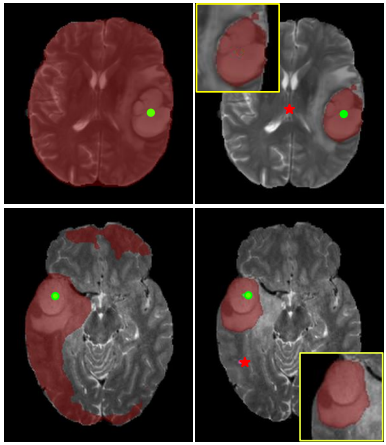

Qualitative Results - Segmentation on medical scans

Few-Shot 3D Volumetric Segmentation with Multi-Surrogate Fusion

Meng Zheng, Benjamin Planche, Zhongpai Gao, Terrence Chen, Richard J. Radke, Ziyan Wu

Medical Image Computing and Computer Assisted Intervention (MICCAI), 2024 [early accept]

We present MSFSeg, a novel few-shot 3D segmentation framework with a lightweight multi-surrogate fusion (MSF). MSFSeg is able to automatically segment unseen 3D objects/organs (during training) provided with one or a few annotated 2D slices or 3D sequence segments, via learning dense query-support organ/lesion anatomy correlations across patient populations. Our proposed MSF module mines comprehensive and diversified morphology correlations between unlabeled and the few labeled slices/sequences through multiple designated surrogates, making it able to generate accurate cross-domain 3D segmentation masks given annotated slices or sequences.